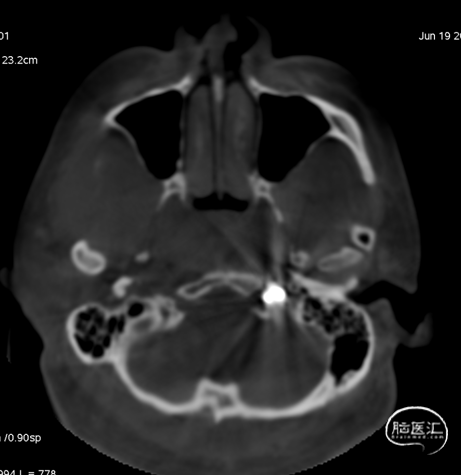

术前CT见左侧眼上静脉扩张

术后铸胶形态及CT下铸胶位置,可见瘘口位于左侧舌下神经管区域。